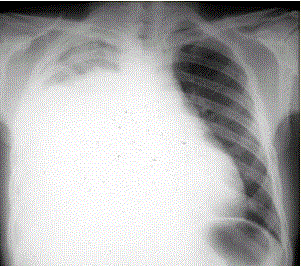

患者男,34岁。进行性胸闷、气促1个月余,伴有干咳、右胸隐痛以及消瘦,无咯血、发热、盗汗、潮热等。(提示 胸部X线检查如图所示)诊断明确后,可...

问题 患者男,34岁。进行性胸闷、气促1个月余,伴有干咳、右胸隐痛以及消瘦,无咯血、发热、盗汗、潮热等。 (提示 胸部X线检查如图所示) 诊断明确后,可考虑的治疗方法是(提示 患者经积极处理后上述症状明显好转。1周后已明确诊断。)

选项 A.外科手术 B.全身化疗 C.抗结核治疗 D.利尿治疗 E.化学性胸膜固定术 F.埋置胸腔导管引流 G.抗感染治疗

答案 BEF